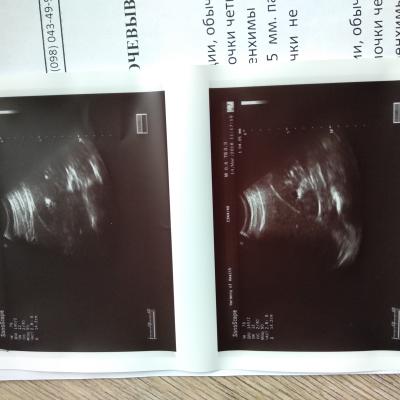

Мучают боли в почках, год назад сделали операцию пиелолитемию слева.

Необходимо дополнительное обследование для уточнения причин возникновения рецидива МКБ и выбора тактики ведения. Но для этого представленных Вами данным не достаточно, чтобы принять решение. Ваш вопрос требует изучения всех имеющихся у Вас медицинских данных. Мы готовы Вам помочь в принятии правильного решения, получения второго мнения на базе . Технически это можно сделать на нашем консультативном портале http://nethealth.ru/. Зарегистрируйтесь на нем, задайте вопрос мне, прикрепите сканы всех документов, которые у Вас имеются.